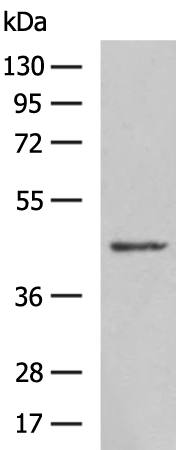

分类: 科研抗体货号: P11640别名: T10应用: WB,IHC反应种属: Human

分类: 科研抗体货号: P11626别名: KRS1; MST2/KRS2; MST1; YSK3; TIIAC应用: WB,IHC反应种属: Human, Mouse